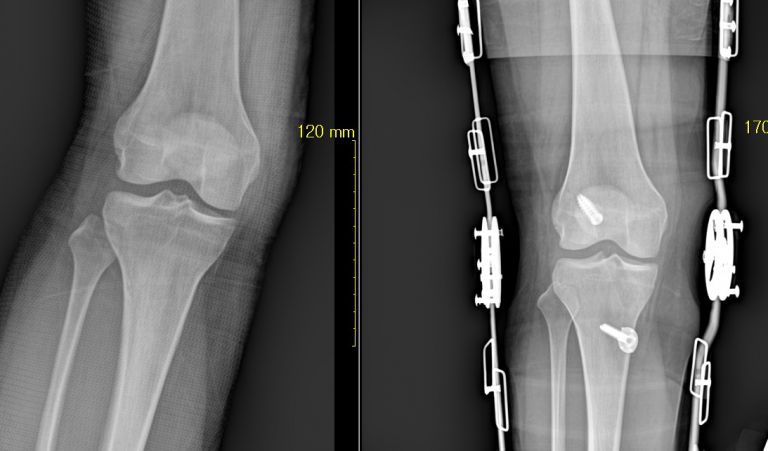

슬관절 내측 또는 외측인대 파열 수술